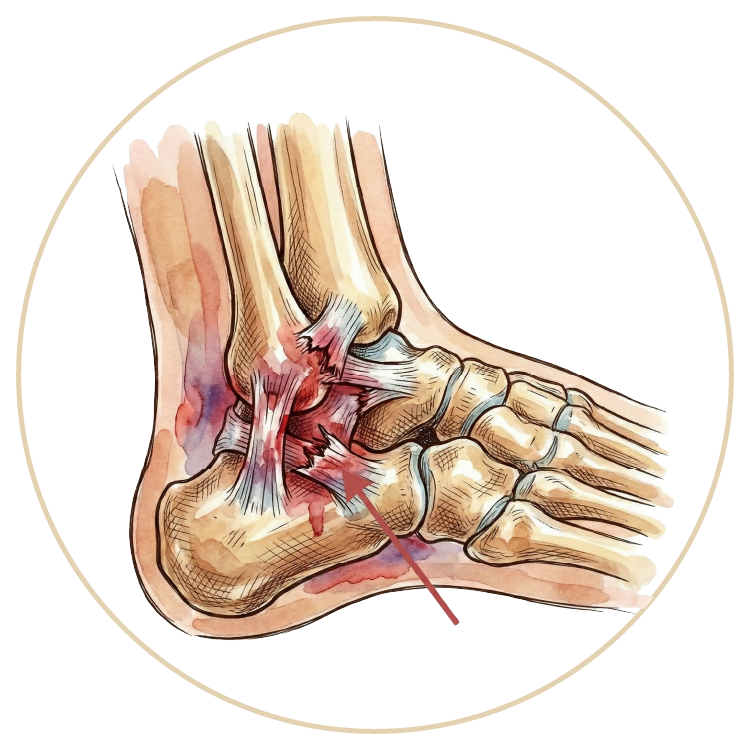

Ayak ve Ayak Bileği Hastalıkları

Ayak Bileği Yaralanmaları

Ayak Bileği Protezi

Ayak Bileği Artroskopisi